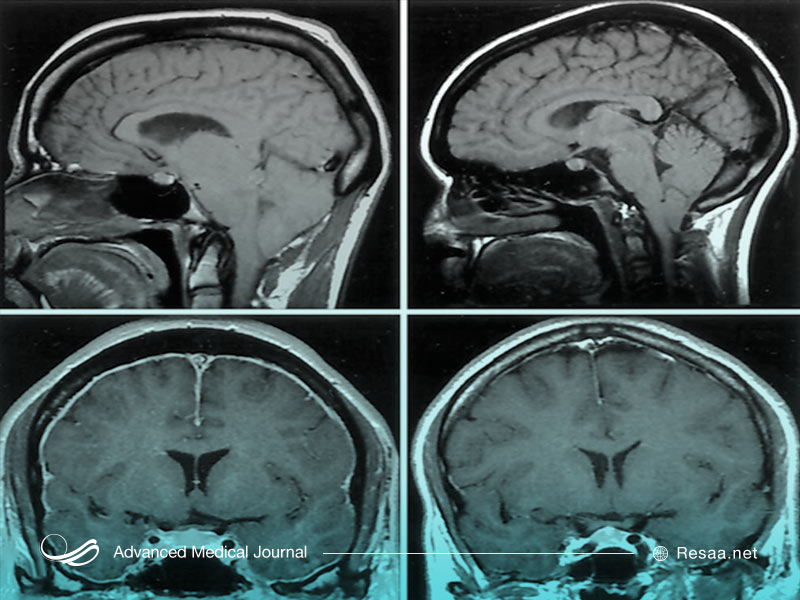

همچنین این امکان وجود دارد که پزشک به منظور کمک به تشخیص بیماری، اسکن تصویربرداری را تجویز کند. این موارد میتواند شامل اشعه ایکس “X-rays”، اسکن MRI و سی تی اسکن “CT scan” باشد. این تصاویر به پزشک شما کمک میکند تا به دنبال ناهنجاری در ساختار استخوان، بافتهای مغز، اندامها و اعصاب باشد.